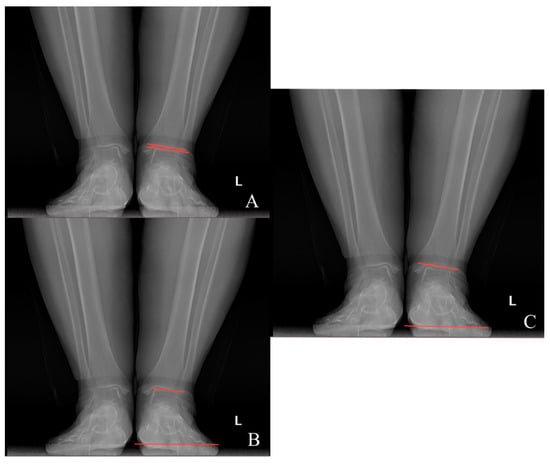

Preoperative and last visit full-leg standing radiographs were evaluated in each patient. Radiological measurements were performed using the picture archiving and communication system software. Two researchers independently measured the selected angles on all radiographs. The study utilized the average of the measured values. The hip–knee–ankle (HKA) angle was defined as the angle between a line drawn from the center of the femoral head to the femoral intercondylar notch and another line from the center of the tibial plateau to the mid-talar dome. The joint line convergence angle (JLCA) was measured as the angle between the femoral and tibial joint lines. The talar tilt (TT) angle was defined as the angle between the subchondral plate of the distal tibial articular surface and the talar dome, with the apex lateral angles positive and the apex medial angles negative. The ground talar dome (GT) angle was between the talar dome and a line parallel to the ground, and the ground plafond (GP) angle was between the subchondral plate of the distal tibial articular surface and a line parallel to the ground, both with apex lateral angles positive and apex medial angles negative.

The HKA, TT, JLCA, GT, and GP angles were measured on the patients’ radiographs (Figure 2 and Figure 3). The preoperative and last visit American Orthopaedic Foot & Ankle Society (AOFAS) scores were evaluated.

Figure 3. (A) Talar tilt angle; (B) ground talar dome angle; (C) ground tibia plafond angle.